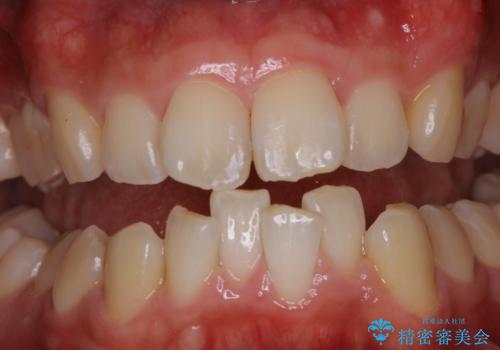

[エアフロー] スプレーの噴射によりしつこい色素沈着やプラークを除去

![[エアフロー] スプレーの噴射によりしつこい色素沈着やプラークを除去の症例 治療後](https://seimitsushinbi.jp/wp/wp-content/uploads/2021/11/IMG_0004-500x350.jpg?v=1636593307)